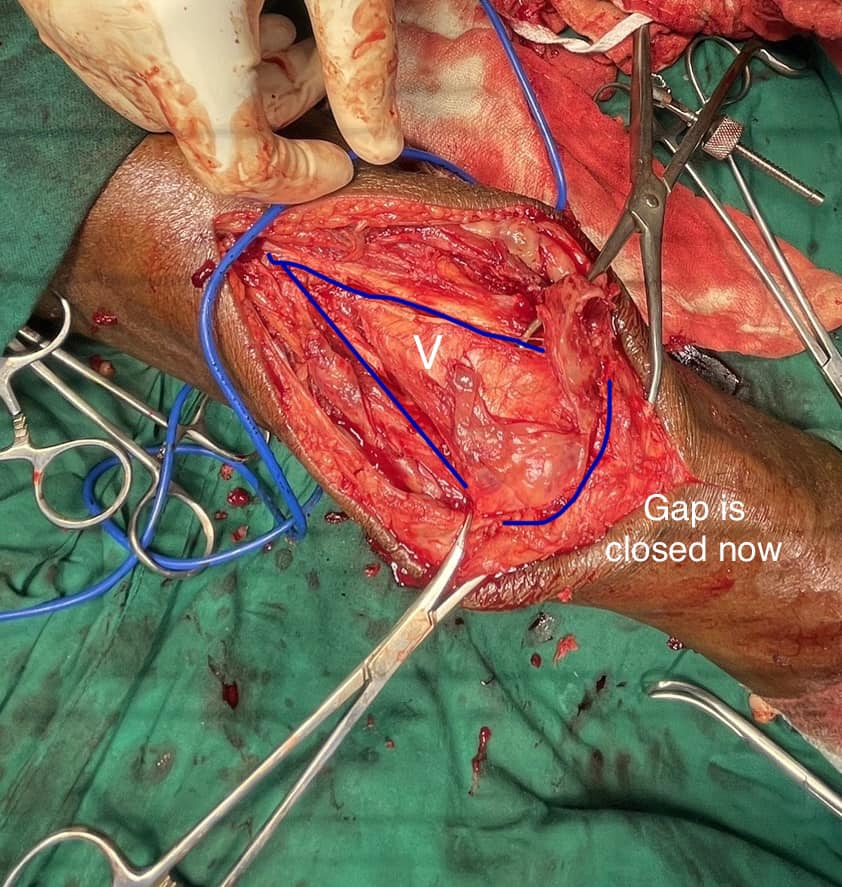

Quadriceps V-Y plasty is a useful tool sometimes needed in extremely bad knees needing total knee replacement or in this case a 6-month-old non union of patella where the two fractured ends are not coming together dude to quadriceps contracture.

If done correctly this surgery helps us to give back normal flexion of the knee and normal power back to the knee extensor mechanism.